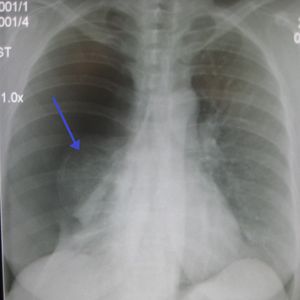

흉부 방사선 사진 촬영으로 진단할 수 있다. 흉부 X선 검사에서 혈관 음영을 동반하지 않는 허탈된 영역은 기흉으로 의심된다.[72] 최대 흡기(숨을 참음) 중에 촬영한 일반 흉부 방사선 사진이 가장 적절한 첫 번째 검사이다.[30] 만기 중에 정기적으로 촬영하는 것은 이점이 없을 것으로 여겨지나,[31] 임상적 의심이 높지만 흡기 방사선 사진이 정상으로 보이는 경우 기흉을 감지하는 데 유용할 수 있다.[32]